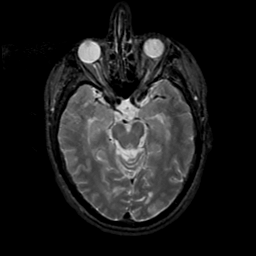

MR Study #19, August 25, 1991 -- Slice #19